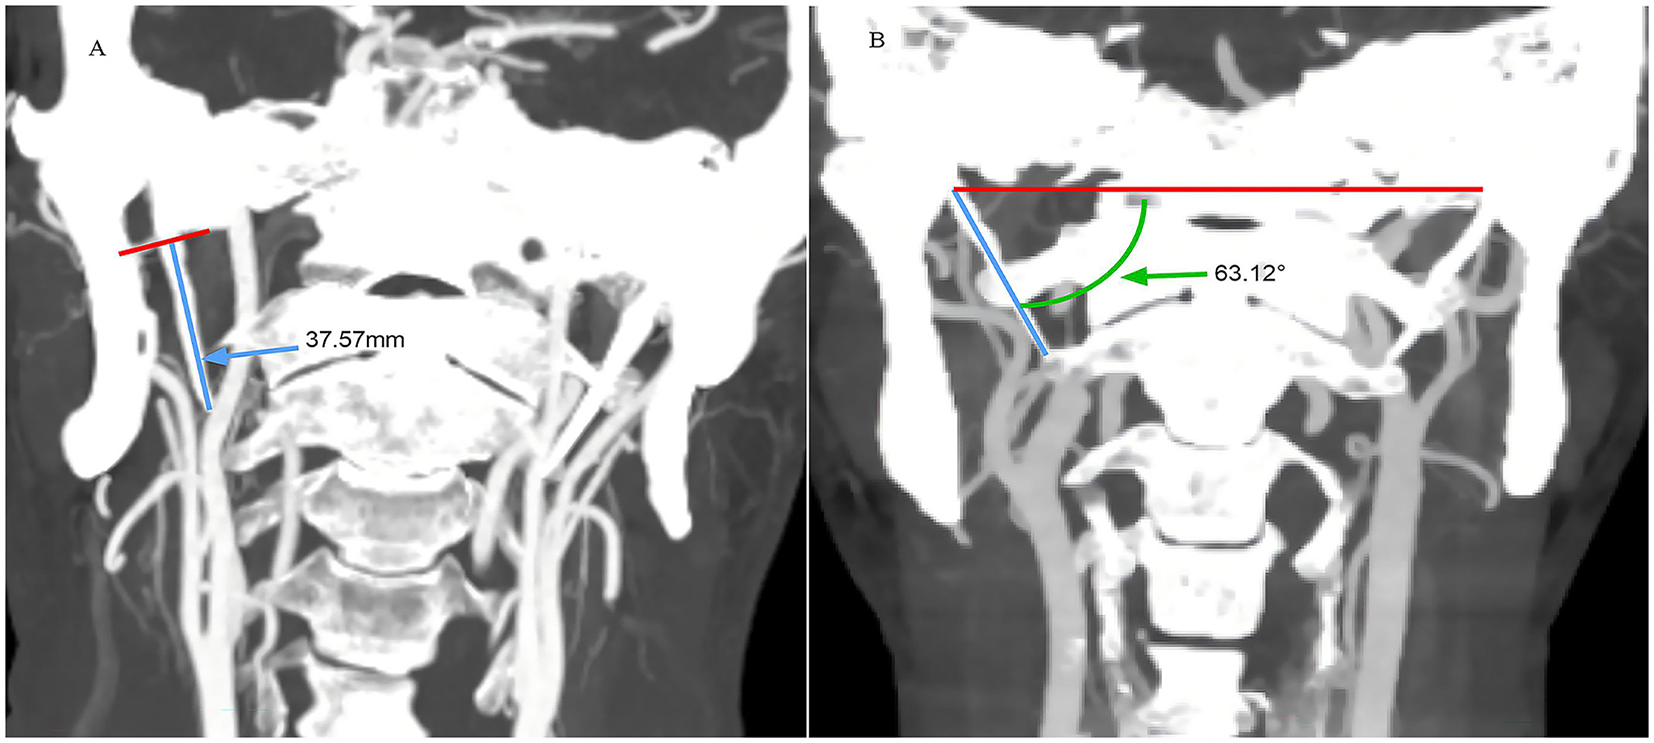

CT imaging was performed using a Siemens 64 slice double helix machine, with patients in the supine position, with the lower jaw elevated and the orbital line perpendicular to the scanning bed. It is generally believed that a large inclination angle can easily compress the internal carotid artery; therefore, inclination angle measurement was performed. Measurements included bilateral styloid process length and angulation of the process relative to midline structures (SP inclination angle) (Figure 1). The angle formed by the line connecting the tip of the SP and the midpoint of the SP root to the horizontal line of the skull base was measured (Figure 1). Multiple studies have used this measurement method to analyze the relationship between styloid process length and internal angle and carotid artery dissection (8, 19). The measurement was performed by two neurology experts (Operator 1 and Operator 2) and the average value was taken.

Figure 1

Examples of measurements of styloid process length [(A) small blue arrow] and styloid process inclination angle [(B) small green arrow].